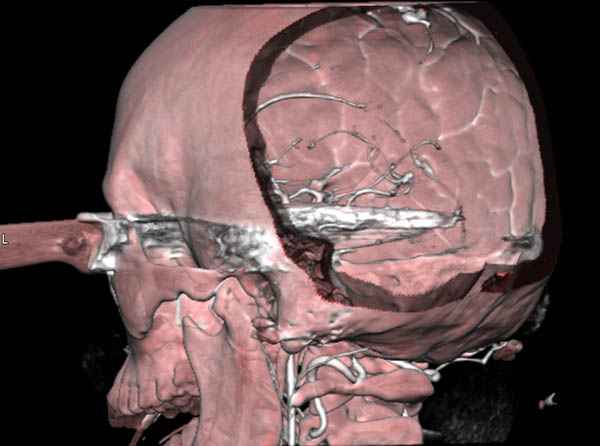

В своих выступлениях я рассказывал, что наши центры в мирное время по пенетрирующим травмам не уступает Ираку или Афганстану, и вот недавно к нам поступила больная 22 лет, травма "ножом в глаз" от бывшей подруги нынешнего "бой френда".

При поступлении в сознании, жаловалась на неприятные ощущения в глазнице.

По протоколу сделаны все необходимые исследования: рентген, ангиограмма с 3Д реконструкцией, где обнаружили что все жизненно важные сосуды не задеты, даже некоторые "сидят" изгибаясь на ноже.

Одним махом нож удалить не удалось, пришлось раскачать и потом двумя руками удалили нож. Рана без кровотечения, обработана и зашита.